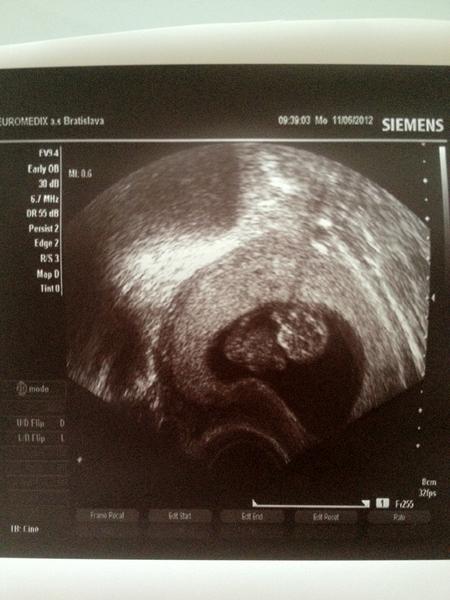

@verry (Sanus Pce) 1.IVF duben/12 (neúspěšné), 14.5. KET (2 E), 11.6. UZV - krásné jedno miminko se ♥

G R A T U L U J E M E ღ 😵 😵 😵